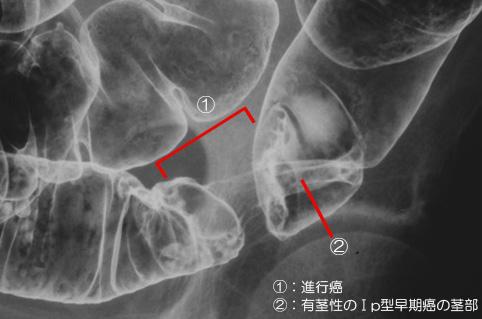

症例提示(所在地,施設名等): 佐賀県・ 佐賀大学医学部放射線科 (水口昌伸先生からの提供症例)

疾患(病理主体)の分類悪性上皮性腫瘍/腺癌

部位(臓器別)大腸/S状

検査方法X-P

腫瘍の肉眼分類1型(腫瘤型)/

病変の最大径(ミリ)30〜34

腫瘍の深達度s(a)

多発腫瘍(同一臓器)有(同時性)